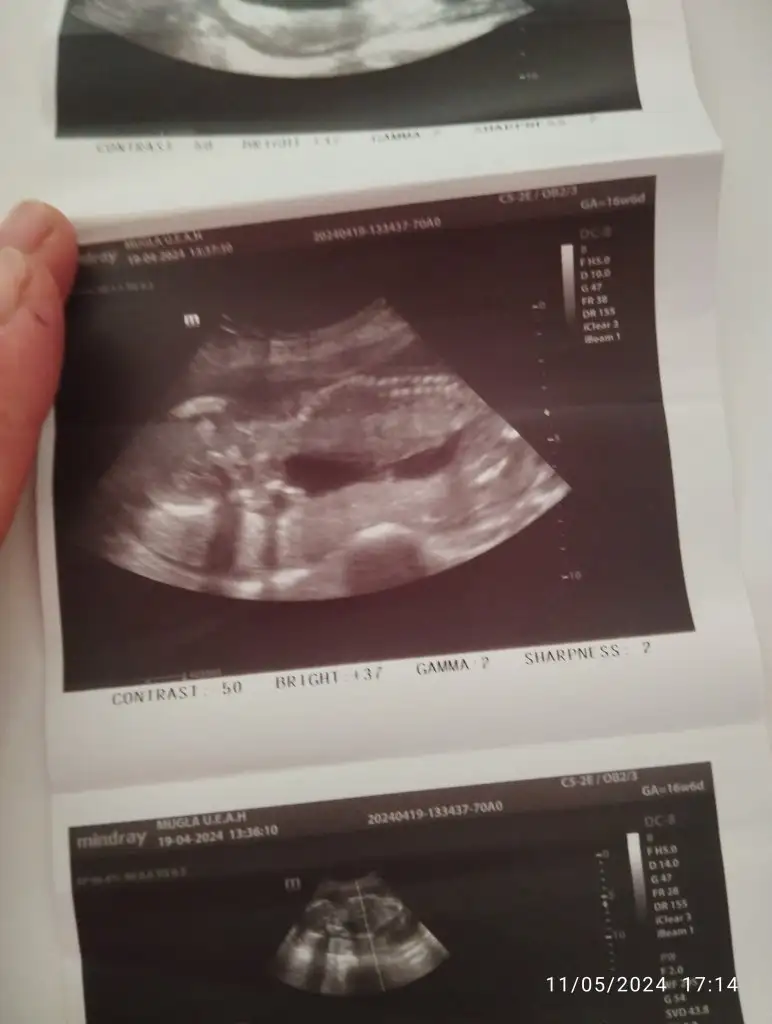

12+6 ydı bir hafta geç döllenme aslında 13+5 olması lazımdı 😂 karından ultrason